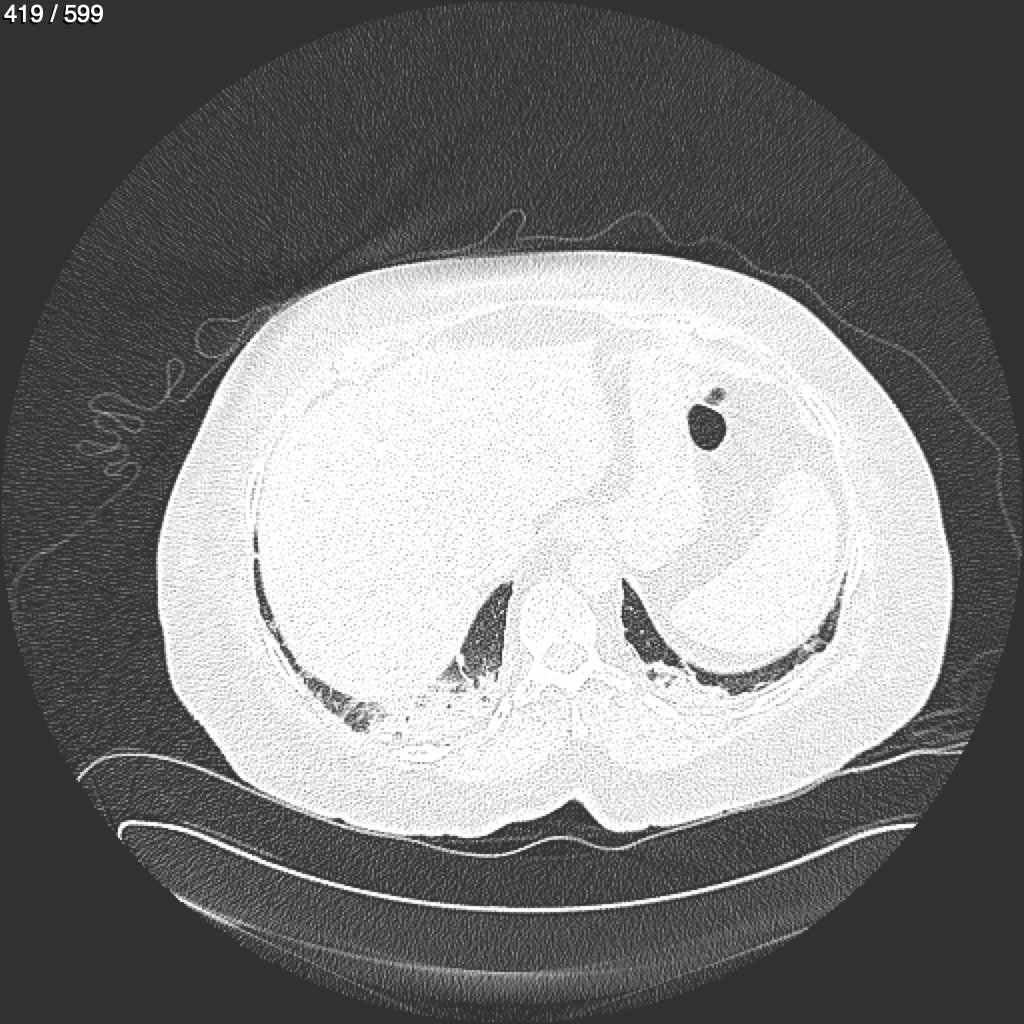

Home G​l​o​r​i​a​ ​G​l​a​d​y​s​ ​B​e​a​s​l​e​y​ ​-​ ​T​ó​r​a​x​ ​T​o​r​a​x​_​S​i​m​p​l​e​ ​(​A​d​u​l​t​o​)